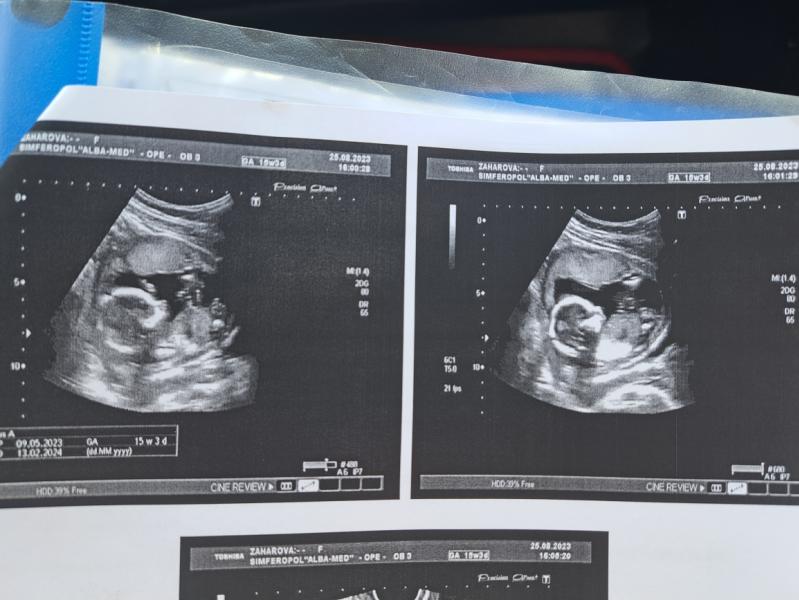

И вот вчера, 25 числа(3-4 фото) , сходила еще раз, что бы узнать пол, малышь решил показать, все прошло хорошо, плацента поднялась, это радует, теперь ждем 3 сентября, будем узнавать!